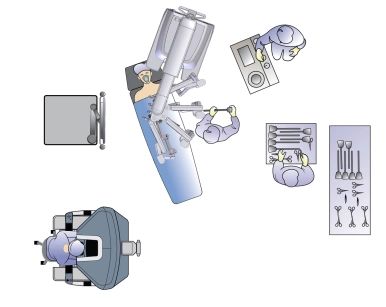

Lehrbeiträge aus den Bereichen der Allgemein- und Viszeralchirurgie, Gefässchirurgie, Gynäkologie, Thoraxchirurgie, Robotik und Handchirurgie Schritt für Schritt in Videos erklärt.

Von Chirurg:innen – für Chirurg:innen

E-Learning Plattform

für Chirurgie